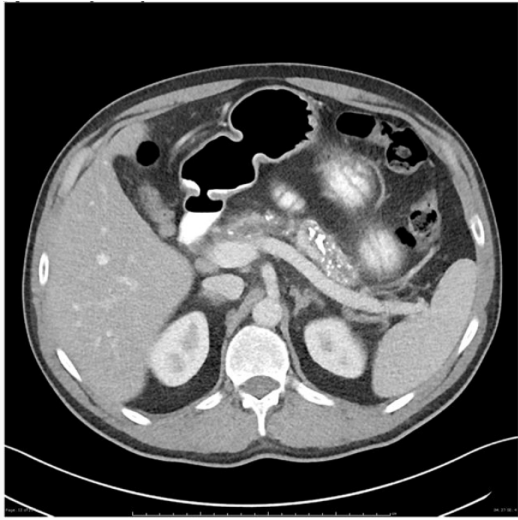

MSL, 55 anos, comparece ao hospital com quadro de dor abdominal, inespecífica, com piora após as alimentações, iniciada há cerca de 10 dias. Refere ser alcoolista crônico; porém, nega qualquer outra comorbidade. Realizada tomografia computadorizada de abdome, como atesta a figura abaixo:

Figura 1 –Tomografia computadorizada de abdome.

Enunciado 4478609-1

Fonte: CPCON.

Qual seria a hipótese diagnóstica compatível com o caso apresentado e os achados de imagem que podem estar associados, além dos que são apresentados no exame?